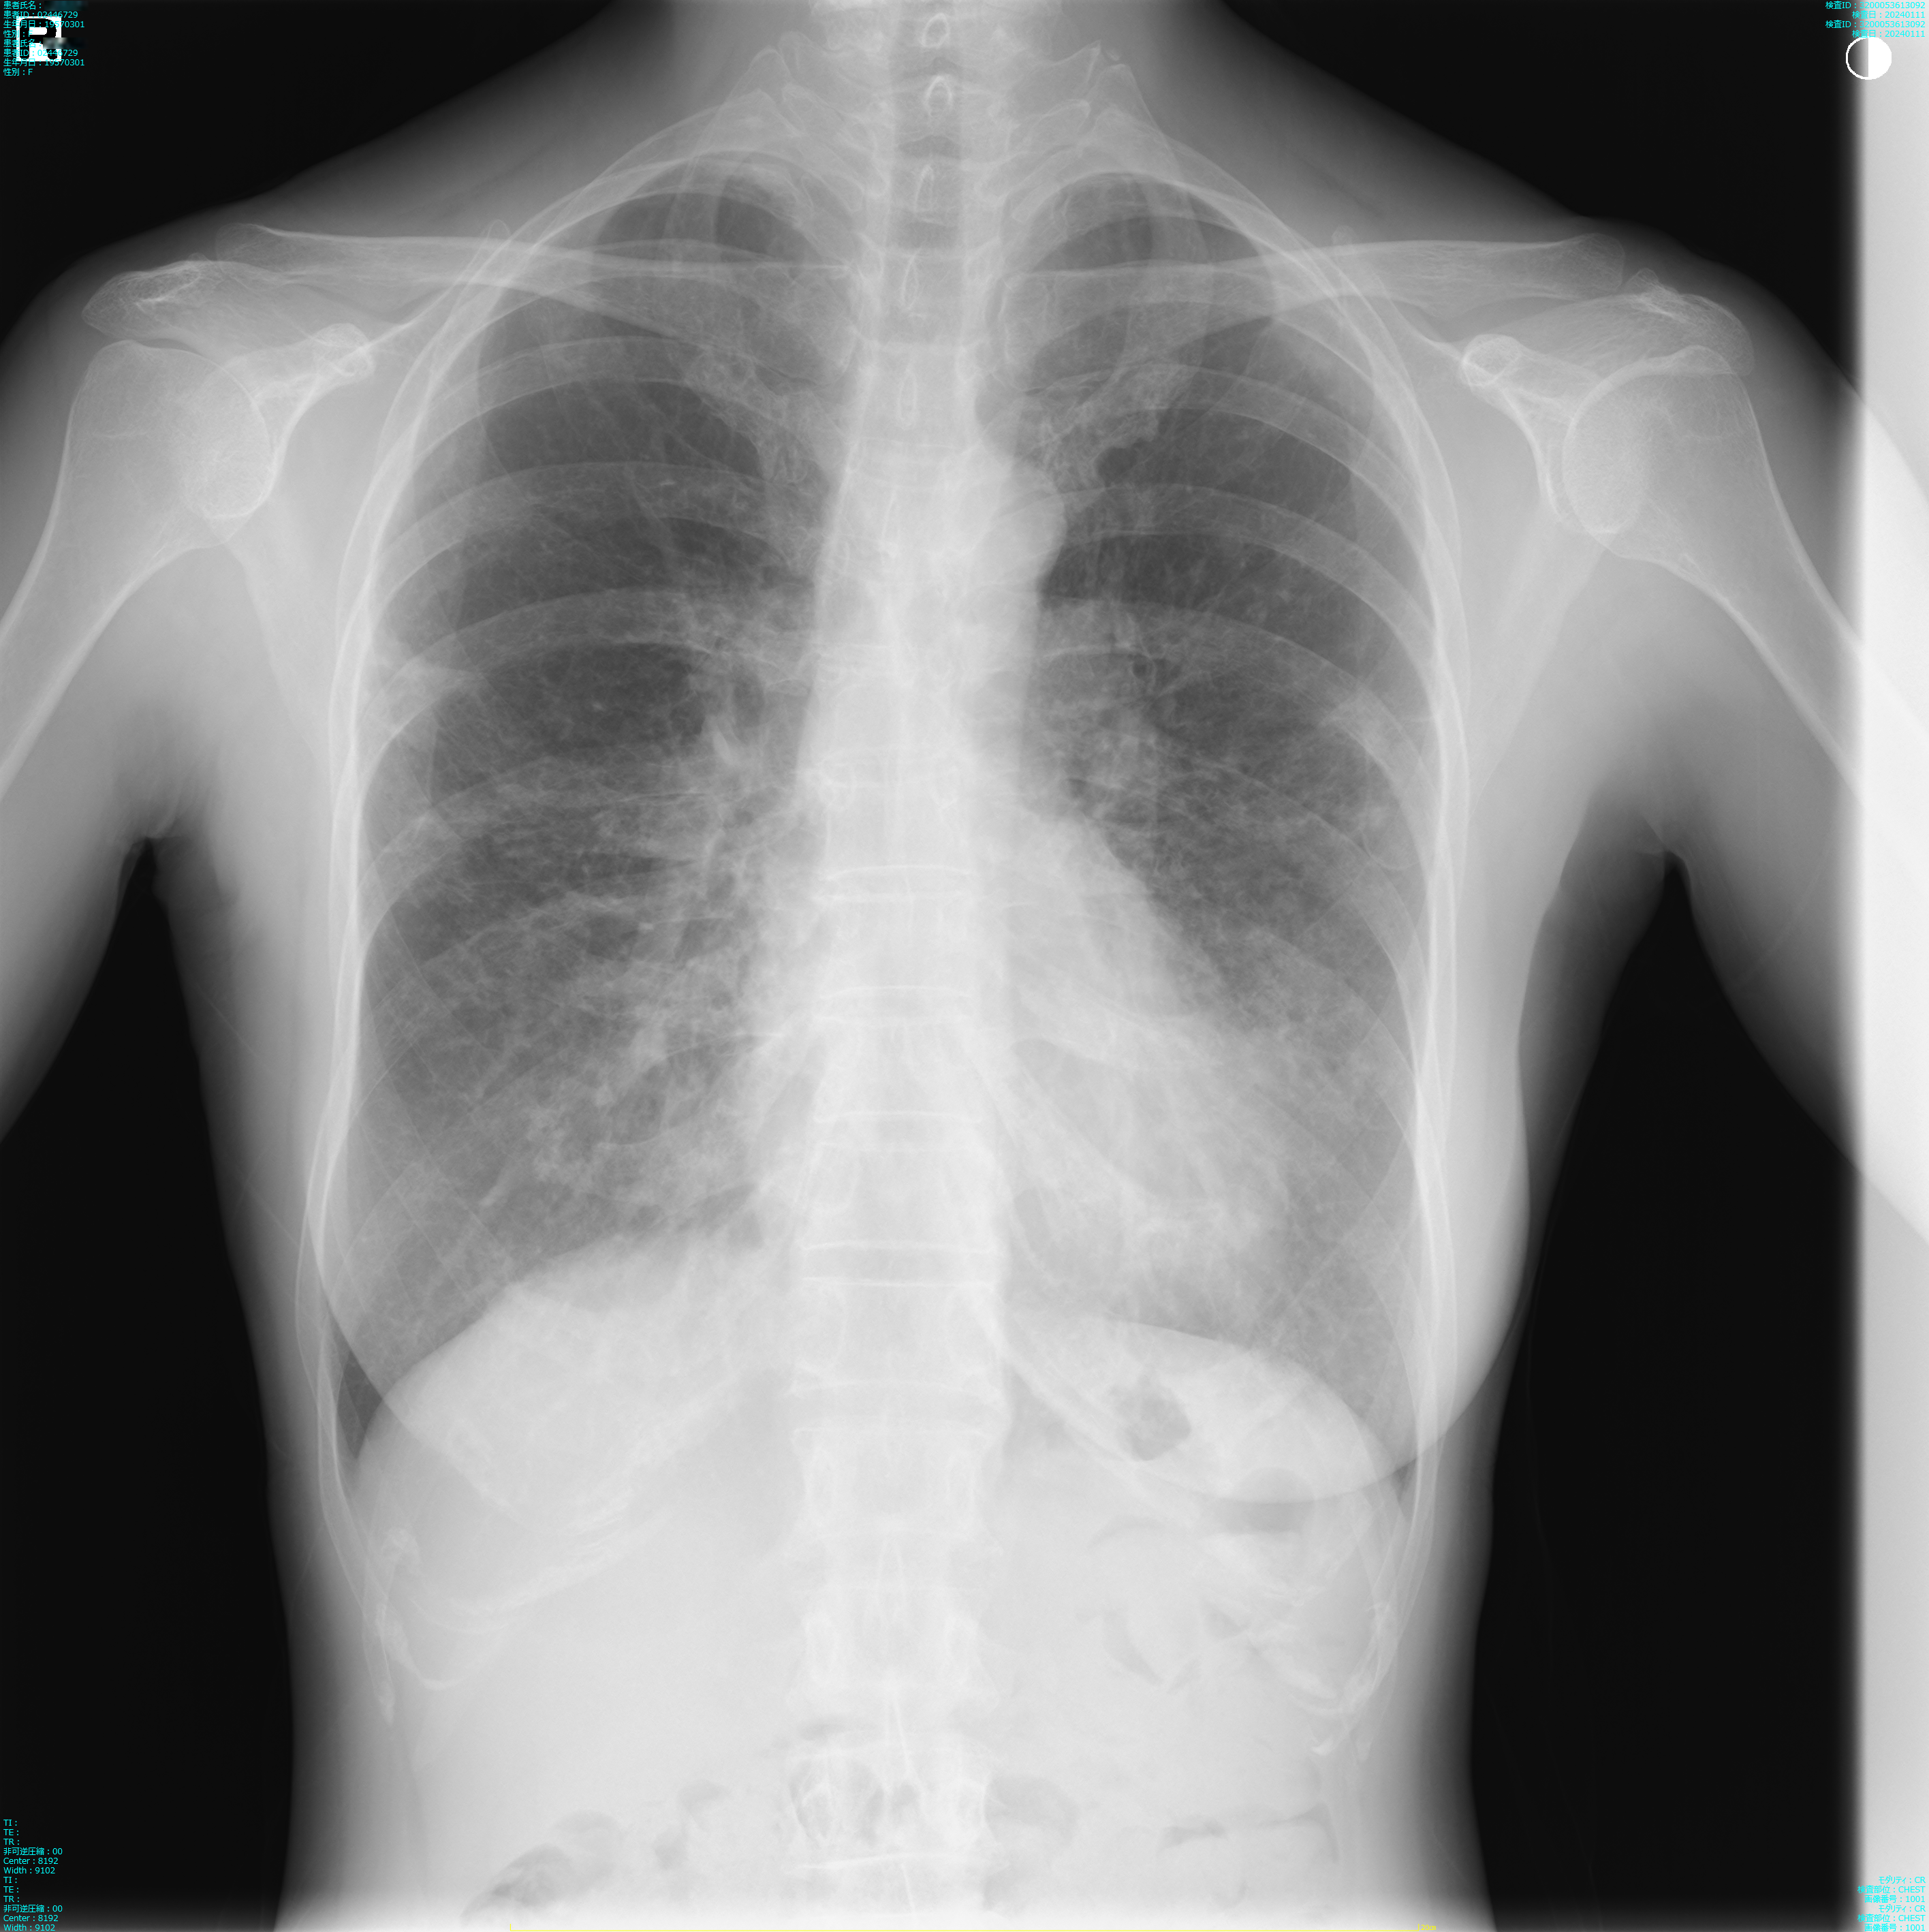

肺X線画像

2023

- 2023.09.21 入院加療の必要ありと診断された画像(国立系病院)